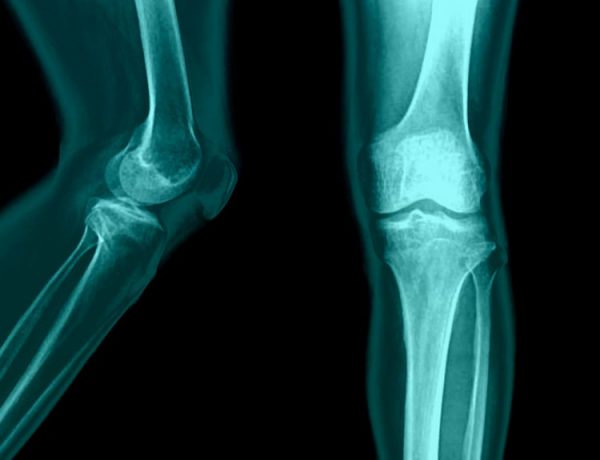

Те врти коленото? Те боли грбот, а понекогаш и колкот?

Најчести причини за артритис

Прашајте некој што мисли дека предизвикува остеоартритис. Најчестиот одговор е стареење, коските стануваат послаби, а…

Остеоартритис & почетни симптоми на болки во зглобовите…

Симптоми Кога се обидувате да ги контролирате симптомите на остеоартритис може да настанат повеќе грешки.…

Остеоартритисот не е резултат само на стареење, туку и на физичката (не)активност